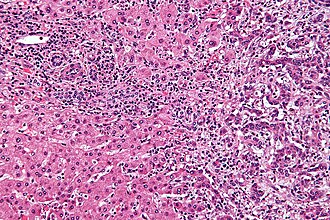

Cholangiocarcinoma. H&E stain. | |

Microscopic

Features:[8]

- Usually an adenocarcinoma, i.e. gland forming with:

- Cuboidal or columnar mucin producing cells, and

- A dense fibrous (desmoplastic) stroma.

Cholangiocarcinoma - low mag. Shows the typical desmoplastic stroma. (WC/Nephron)